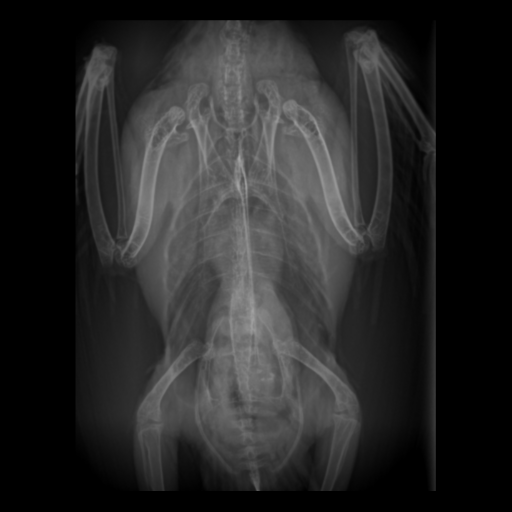

○レントゲン検査

視診・触診では見えない体の中の状態をチェックします。

- 骨・関節

- 呼吸器(肺、気管、気嚢)

- 消化器(そのう、食道、胃腸、クロアカ)

- 肝臓

- 心臓・血管

- 腎臓

- 生殖器(精巣、卵巣、卵管)

- 脾臓

造影検査